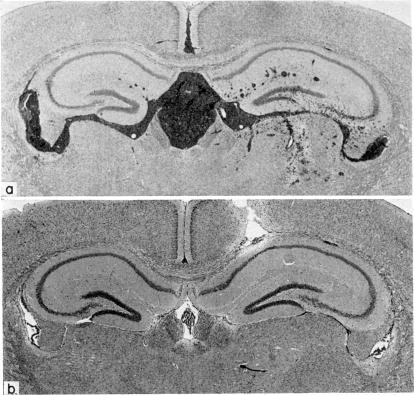

Following intracerebral (i.c.) inoculation DBA/2 (H-2d) mastocytoma cells (P815) grow to concentrations of greater than 10,000/mul in cerebrospinal fluid (CSF) of H-2 compatible BALB/c mice, but are completely eliminated from 90% of such animals within 12 days. A similar pattern occurs in allogeneic C57BL (H-2b) and random-bred WEHI mice, whereas syngeneic DBA/2 mice die within 7 days from unrestricted tumour growth. Rejection in BALB/c mice is enhanced by prior exposure to the tumour, but is severely depressed by pretreatment with cyclophosphamide. Leucocytes responsible for eliminating the mastocytoma are apparently not active against sarcoma 180 cells injected simultaneously. Subsequent to intraperitoneal inoculation with mastocytoma cells both BALB/c and C57BL mice generate significant cytotoxic activity in spleen, as measured by an in vitro 51Cr release assay. Cytolysis is abrogated by prior incubation of spleen cells with AKR anti-O ascitic fluid and complement, but not by normal AKR ascitic fluid and complement. Following i.c. exposure, however, much lower levels of cytotoxic activity are found in spleen, though specifically sensitized lymphocytes are also present in lymph nodes of the cervical chain.